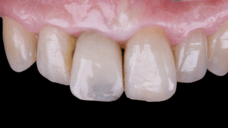

After an appropriate healing period, the definitive prosthesis was planned and delivered. A screw-retained zirconia crown was fabricated to ensure long-term durability, optimal esthetics, and retrievability. Zirconia was selected for its mechanical strength and excellent esthetic properties, blending seamlessly with the adjacent natural dentition in both form and color.

The final crown was designed to maintain the gingival architecture that had been shaped by the provisional. Special attention was paid to the emergence profile, contact points, and translucency to achieve harmony with the patient’s smile. The definitive restoration provided functional stability and esthetic integration, fulfilling the patient’s expectations for a fixed and natural solution.